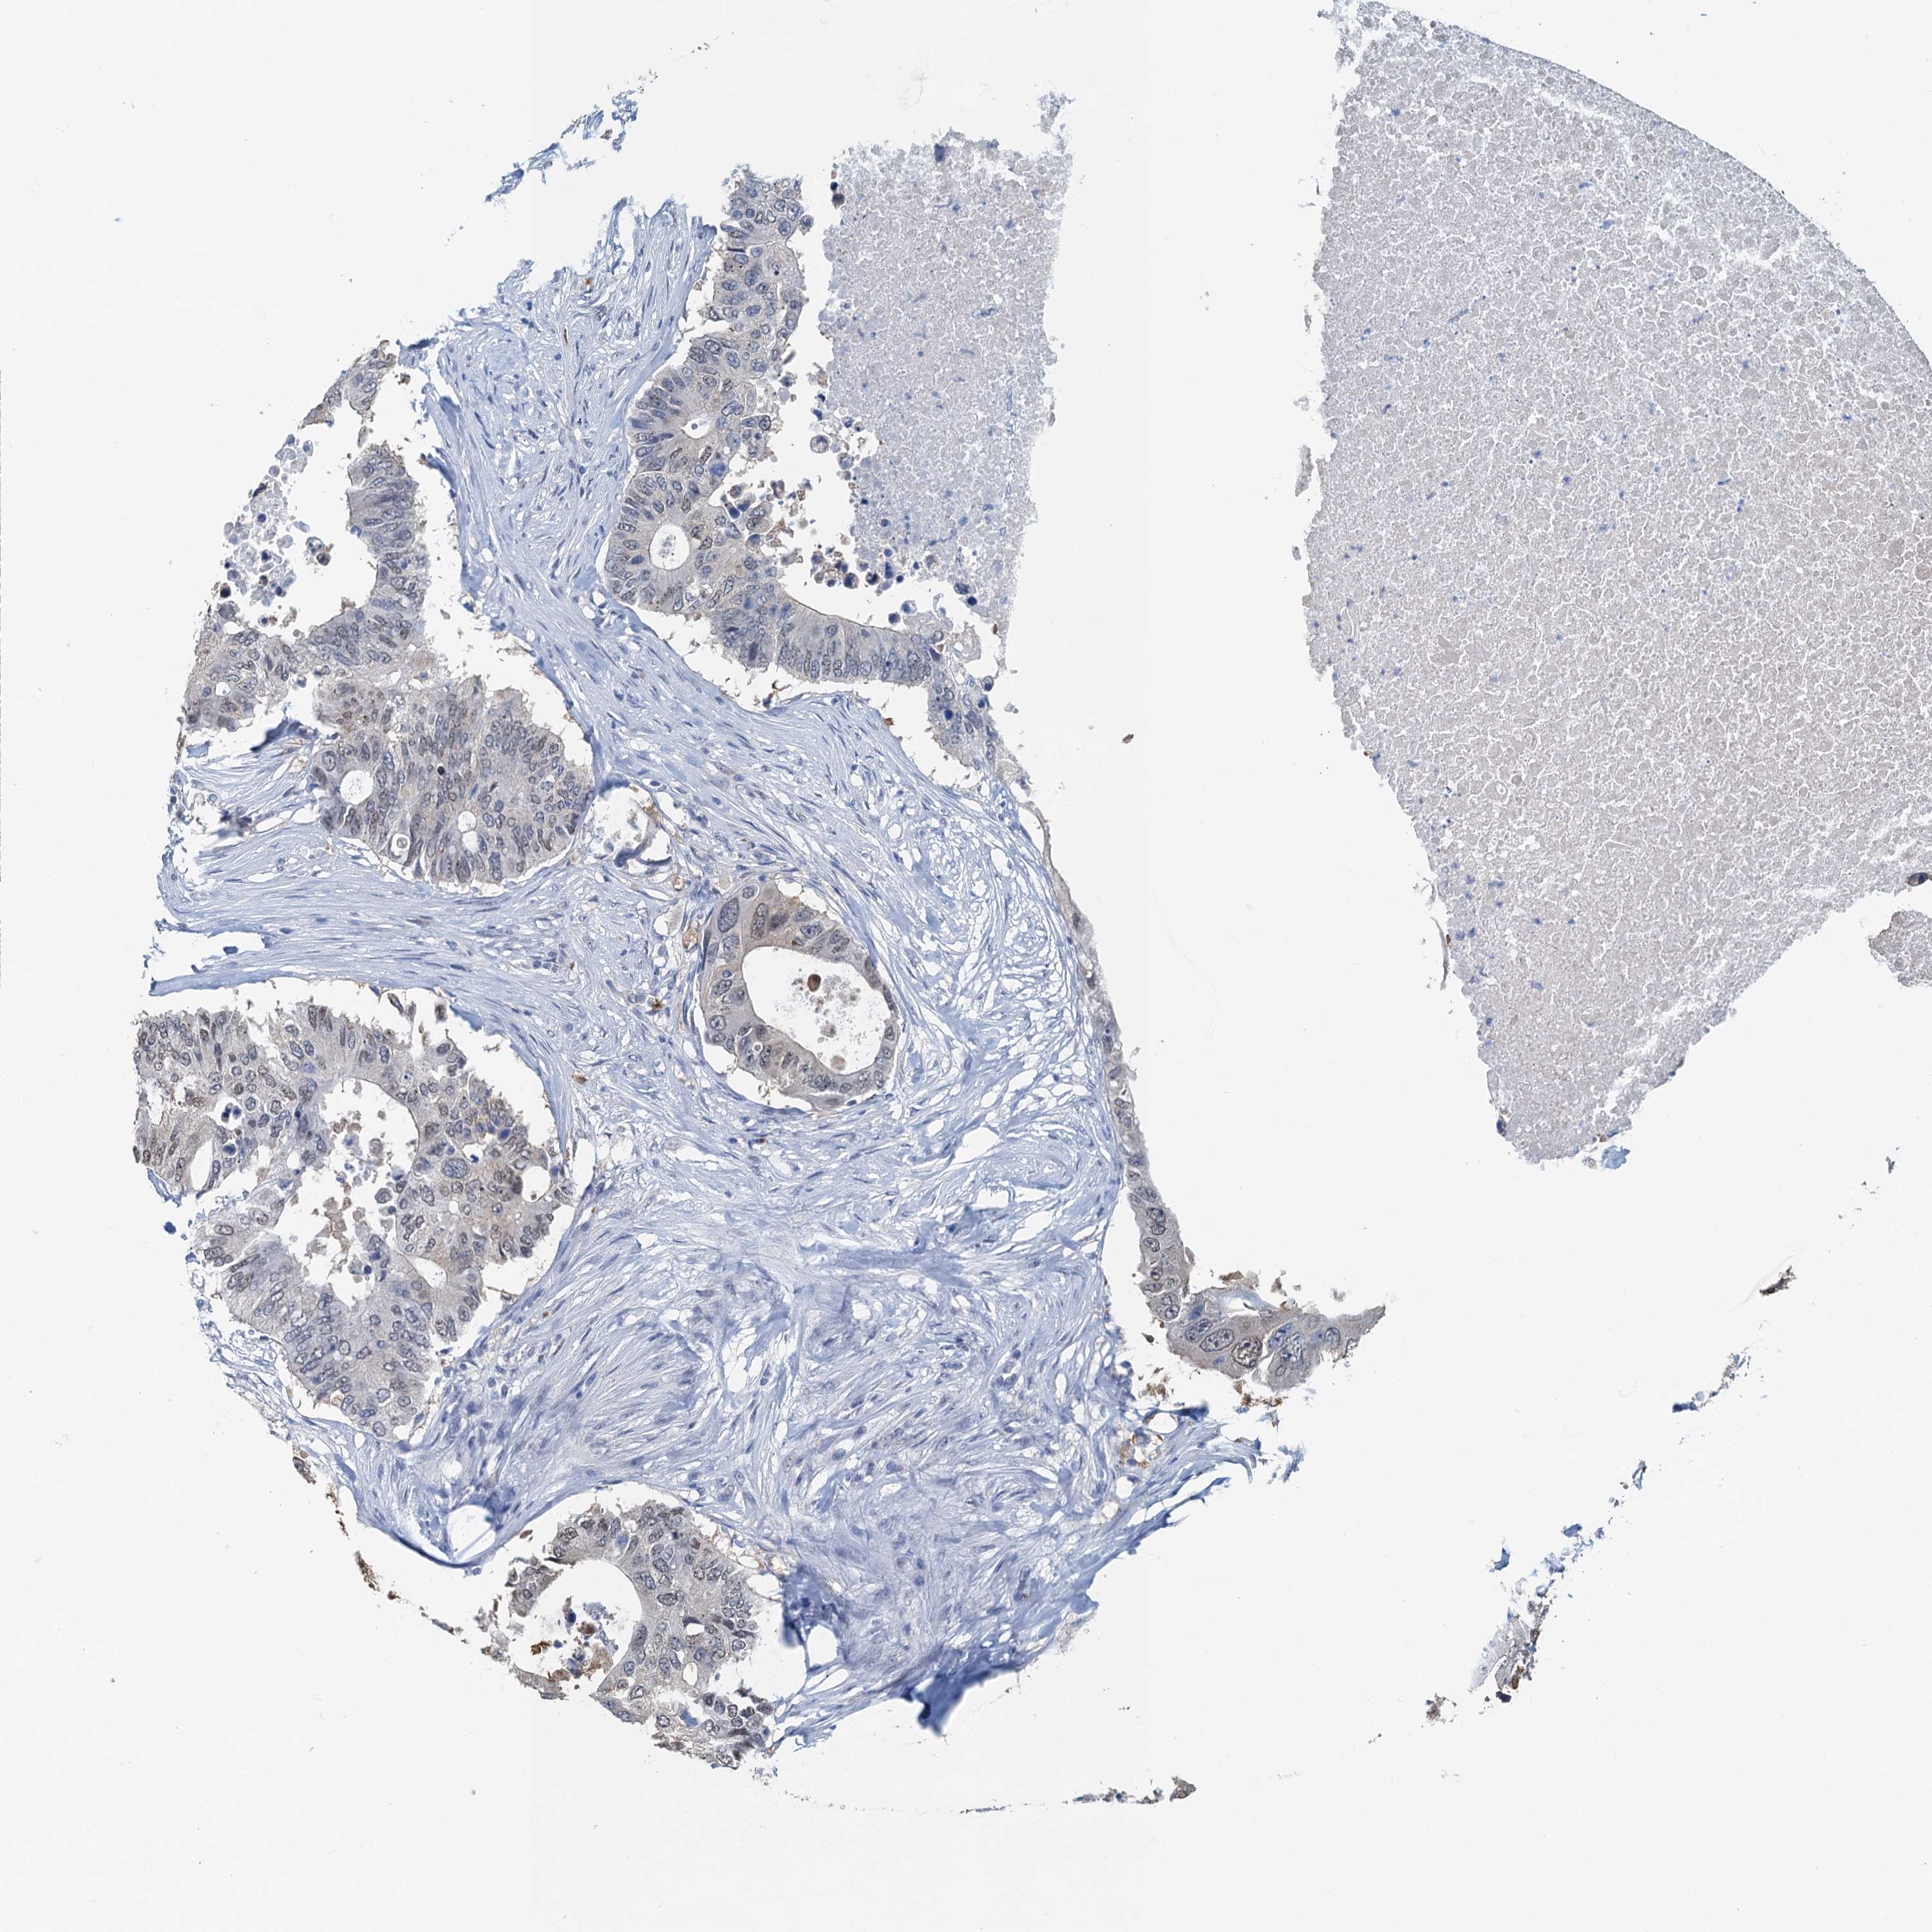

AHCY

CANCER COLORECTAL CANCER Show tissue menu

Colorectal cancer

Human cancer

Colon adenocarcinoma